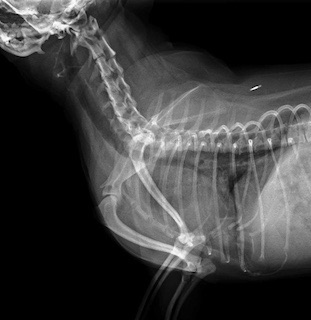

3歳チワワ、頸部気管虚脱

最近症例報告出来ていなかったので報告します。症例は3歳の若いチワワなのですがホームドクターで1歳の時にすでに気管虚脱と診断されています。初診時で頸部気管虚脱グレード3-4と診断しています。手術適応症例でした。またレントゲンでは後天的と思われる漏斗胸も確認出来ました。

レントゲンでは確認出来なかったのですがこの症例は術中に肺ヘルニアを確認しました。咳や胸腔内圧が高かった状態を推察しました。気管支鏡でも重度の狭窄を確認して手術しました。